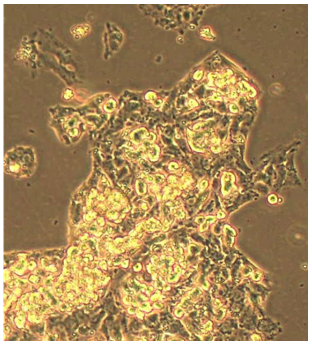

A CRISPR-Cas9–engineered cell line carrying a mutation in the R2-box region of the R2 gene (within the ERE-homologous 5′UTR) exhibits markedly reduced R2 transcript and protein levels. These cells display slower growth and severely impaired HBV infection and replication, making them a valuable model for studying R2 regulation, HBV infection, and pathogenesis.

Growth Properties |

Adherent, epithelial |